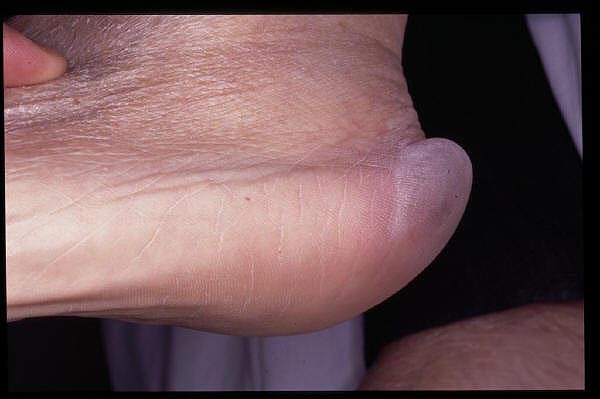

Malformación congénita de pie izquierdo.